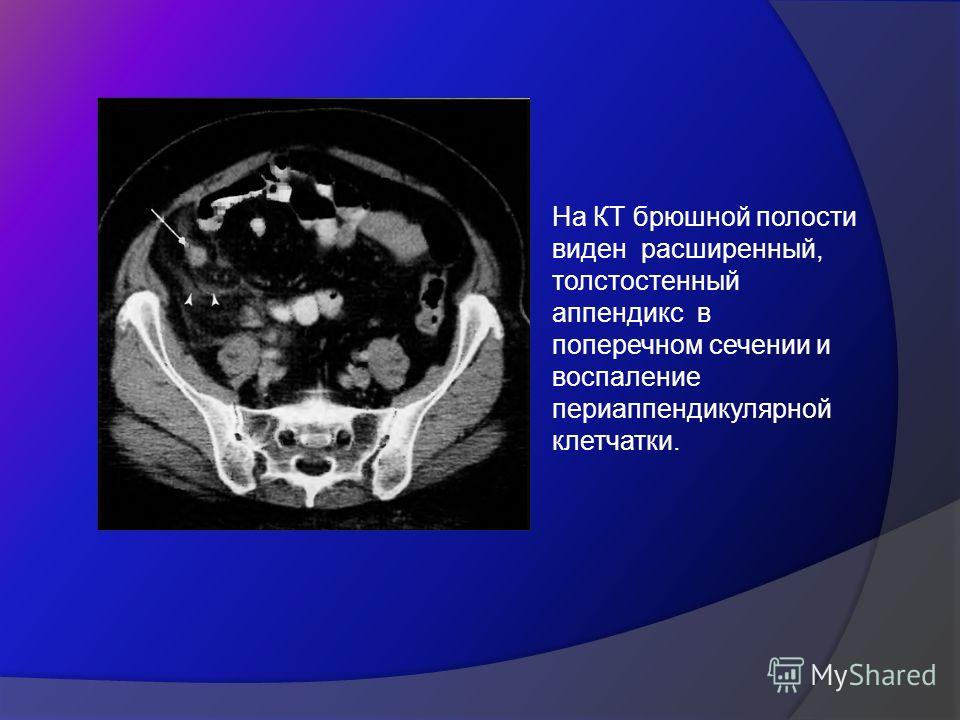

КТ-исследование абсцесса малого таза: Визуализация и диагностика